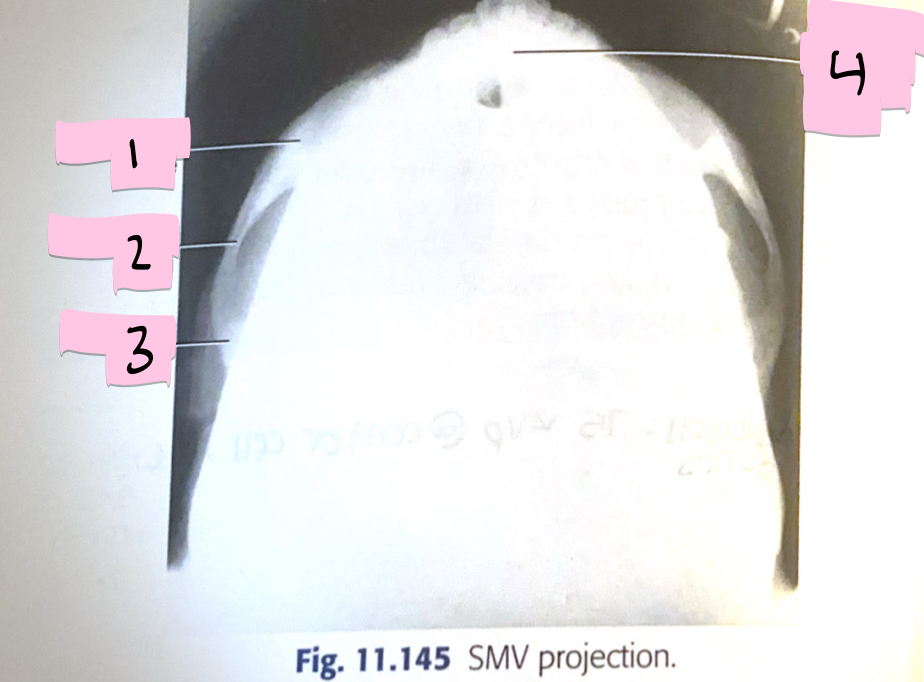

What is 1 pointing to?

Zygomatic bone

What is 2 pointing to?

Zygomatic arch

What is 3 pointing to?

Temporal bone

What is 4 pointing to?

Mandibular symphysis